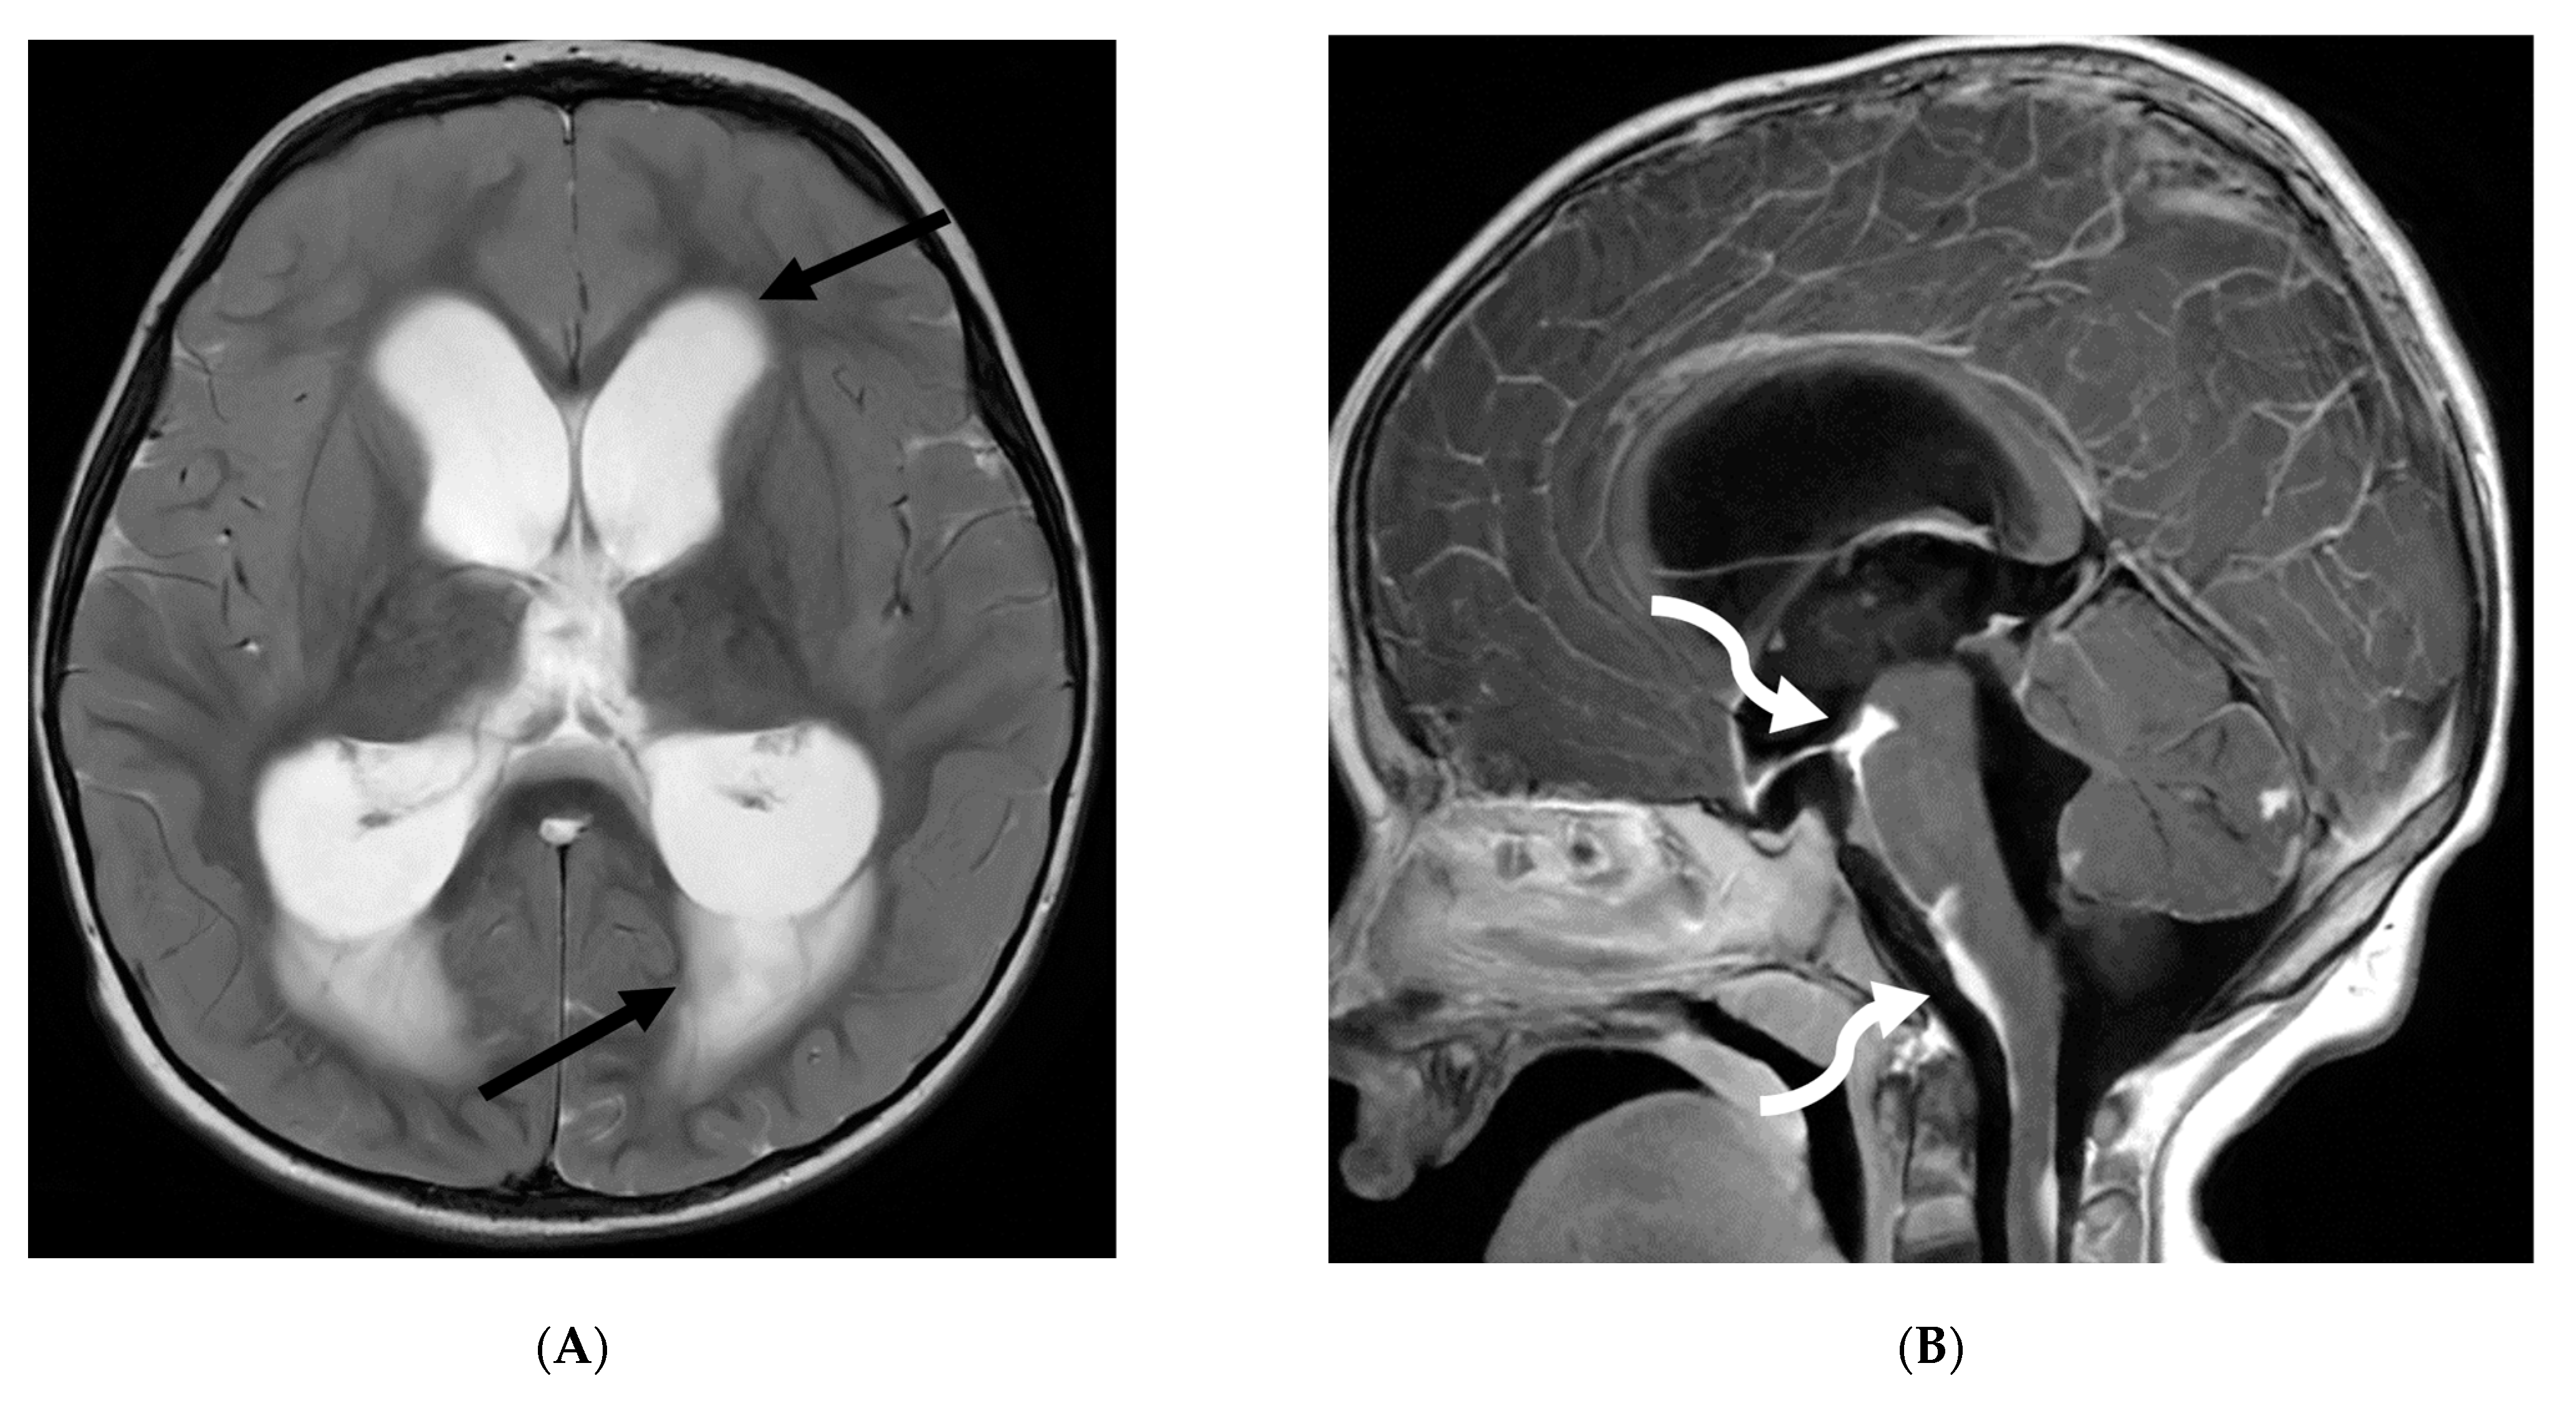

3.8. Intracranial Hypotension (IH)

Intracranial hypotension in children is frequently secondary to iatrogenic causes including lumbar punctures, craniospinal surgeries and ventricular shunt drain pressure changes [64]. Spontaneous causes are commonly connective tissue disorders such as Marfans and Ehler Danlos syndromes. Dural tears and meningeal diverticula have been demonstrated in these cases [65]. Beyond headaches, IH can manifest with nausea, vomiting, light sensitivity (photophobia), and stiff neck [66].

MRI features of IH can be explained by the Monroe-Kellie doctrine, which states that the intracerebral volume including blood, CSF and brain parenchyma remain the same. Thus, a decrease in CSF volume promotes dilatation and rounding of the venous sinuses, subdural fluid collections along with dural (pachymeningeal) enhancement which occurs due to vascular engorgement and transudation of fluid into it [67]. Hyperemia of the pituitary gland occurs which may mimic hyperplasia or pituitary tumor. Brainstem slumping or downward displacement of the brainstem, defined as red nuclei below the tentorium and low lying third ventricle below the sella, are highly specific indicators of IH, observed in half the cases. A pontomesencephalic angle of less than 50 degrees and mamillo pontine distance of less than 5.5 mm are sensitive and specific parameters to suggest IH [66].

With regard to spine imaging, in addition to the intracranial features of dural enhancement, venous engorgement and subdural collection, unique findings include meningeal diverticula, dural ectasia and C1–C2 sign (Figure 8 and Figure 9). Additionally, a CT myelogram may identify the precise location of the CSF leak which can be sealed off with a blood patch [65,68].

Figure 8.

Sagittal T1 (A), post axial T1 (B,C), axial CT myelogram (D) and technetium 99 m DTPA SPECT-CT (E): 16-year-old with Gorham’s disease. There is cerebellar tonsillar herniation and decrease in prepontine cisterns (white arrows). Significant increase in the size of the venous sinuses (dashed arrow). Diffuse pachymeningeal enhancement is seen (black arrows). Cystic-appearing foci at the skull base are in keeping with lymphangiomatosis with contrast pooling into the lytic lesion (curved arrow). Abnormal radiotracer extravasation in the left clival region correlating with lytic lesion (open arrow). Features are in keeping with intracranial hypotension secondary to CSF leak.

Figure 9.

Sagittal T2 FS (A), sagittal (B) and axial (C) T1 post contrast: 3-year-old with neck pain post LP. There is diffuse epidural thickening, with increased T2 signal and enhancement, throughout the cervical, thoracic and lumbar spine (white arrows). Several prominent flow voids are seen within the anterior epidural thickening in the upper cervical region (dashed arrow). There is also increased high T2 signal between the occiput and posterior arch of C1, and between the posterior arch of C1 and spinous process of C2 (curved arrows) in keeping with “C1–C2 sign”. Findings are related to intracranial hypotension post lumbar puncture.